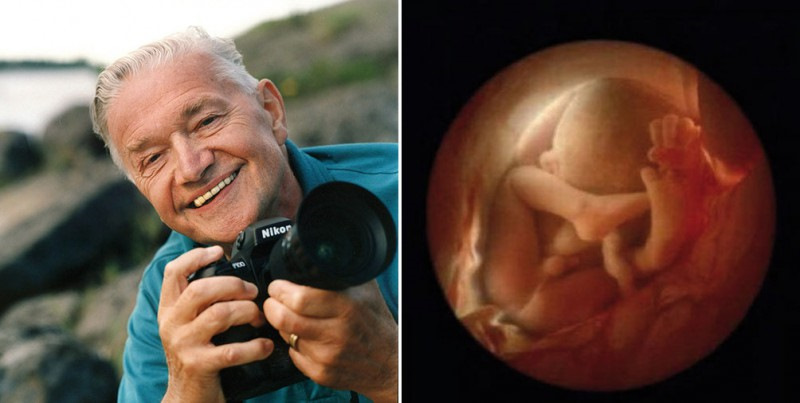

Снимки Леннарта Нильсона: развитие ребенка в утробе

Раздел: Мудрость в фокусе